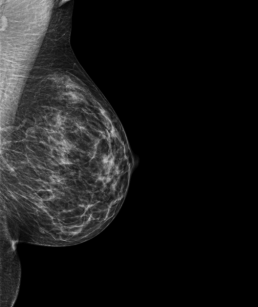

Patiente de 45 ans vient pour examen d’une masse dans le sein droit.

Mammoscreen ne détecte pas d’anomalie.